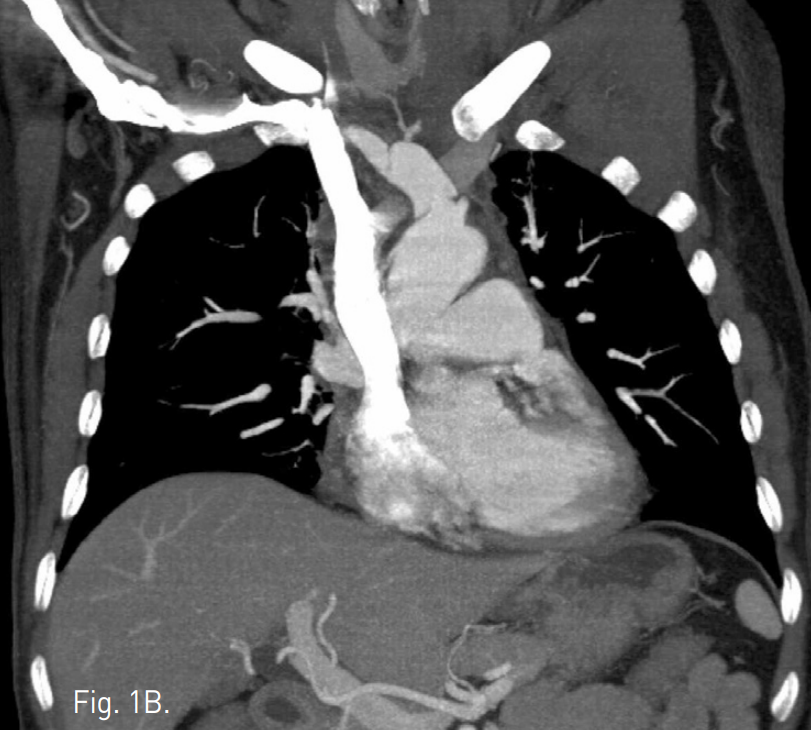

Fig. 3

A, B. On axial (A) and coronal MIP (B) images of follow up CT scan 2 weeks later, thelesion of right brachiocephalic trunk has been completely excluded. Both common carotid and right subclavian arteries are normally visualized.